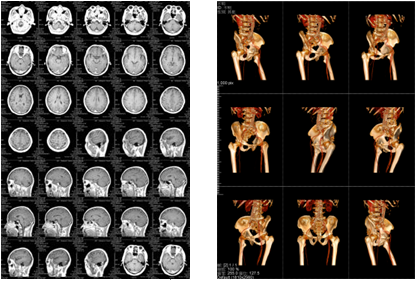

該三甲醫(yī)院放射科負(fù)責(zé)日常CT、核磁共振影像的輸出,平均的日打印量在1000張左右。在導(dǎo)入解決方案前,該放射科的影像輸出使用干式膠片打印傳統(tǒng)膠片,輸出設(shè)備價(jià)格不菲,而且傳統(tǒng)膠片價(jià)格更是高昂。另外,傳統(tǒng)膠片不能實(shí)現(xiàn)彩色輸出,醫(yī)生必須在背光板上進(jìn)行診斷,膠片本身還含有重金屬等有毒物質(zhì),污染環(huán)境。為此,柯尼卡美能達(dá)向?qū)I(yè)供應(yīng)商采購(gòu)了DICOM轉(zhuǎn)換服務(wù)器和符合醫(yī)院要求的打印膠片紙,可實(shí)現(xiàn)三維打印,打印的影像可直接在自然光下觀看,便于醫(yī)生診斷;膠片紙的成本是傳統(tǒng)膠片的三分之一而且不含毒物質(zhì),既節(jié)省成本又綠色環(huán)保。

膠片紙輸出樣張示意